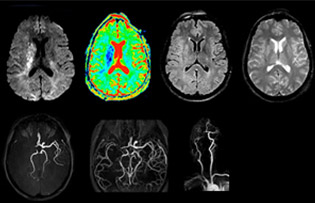

“The biggest challenges are properly characterizing the lesion and giving the surgeon all the information needed, such as the location of vessels and functional areas. Sometimes a very comprehensive exam is necessary, such as when a mass has been discovered at another hospital after which the patient is referred to us. We then do both lesion characterization and preoperative imaging in one exam, so both morphologic and functional assessment. For morphologic assessment we will use pre- and post-contrast T1-weighted imaging, FLAIR to assess infiltration, and diffusion. For functional characterization we will perform perfusion, spectroscopy, and susceptibility weighted imaging to look for micro vessels or micro hemorrhage inside the lesion[4]. For preoperative imaging we perform specific morphologic imaging that is compatible with the navigation system; depending on the location of the tumor, we would do fMRI or DTI.”

“Ingenia provides great flexibility in the parameters setting. We can tune a sequence the way we want,” says Dr. Savatovsky. “For example, in a stroke exam we use a FLAIR sequence of about two minutes instead of the four-minute FLAIR we use for MS. The diffusion is 30 seconds, the T2*-weighted scan is 30 seconds, the angiography scan time is less than one minute. Ingenia is a great scanner in that situation; even with these fast sequences we can achieve good images with good SNR. When the first sequence tells us that it’s not an ischemic stroke but a hemorrhagic stroke, we may switch to a time-resolved angiography to look for vascular malformations and venous thrombosis.

“Every center is different, but for me the ideal protocol for stroke includes diffusion weighted imaging, FLAIR, and fast susceptibility imaging,” says Dr. Savatovsky. “Our fast susceptibility weighted imaging takes 50 seconds, so it’s as fast as T2*-weighted imaging. It visualizes hemorrhage but also the clots. We also do 3D MR angiography that provides information on cervical and brain vessels. If the patient does not need immediate treatment, or if additional information is needed to decide on treatment, we might also add perfusion imaging and post-contrast T1-weighted imaging.”